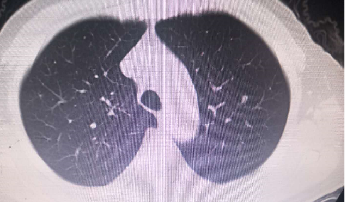

胸部CT对比:

瑞戈非尼治疗前

瑞戈非尼治疗3个月

瑞戈非尼治疗8个月